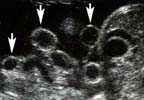

- Pas de membrane herniaire,

- Taille du collet (2 à 4cm) : plus le collet est petit, plus les risques d’étranglement existent,

- Anses intestinales flottant dans le liquide amniotique :

¤ Tout ou partie de l’intestin peut être intéressé, plus volontiers le grêle,

¤ Estomac 1 fois/3, parfois annexes ou testicules, rarement foie,

¤ L’intestin peut flotter librement dans le liquide amniotique avec distinction nette, intestin grêle - gros intestin, anses animées de péristaltisme (bon pronostic ?) et lumière intestinale visible,

¤ Les anses intestinales peuvent au contraire être oedématiées, épaissies et dilatées, ou collabées, rétractées sans péristaltisme avec apparition en intra abdominal d’une dilatation du tube digestif restant animée de péristaltisme (mauvais pronostic ?),